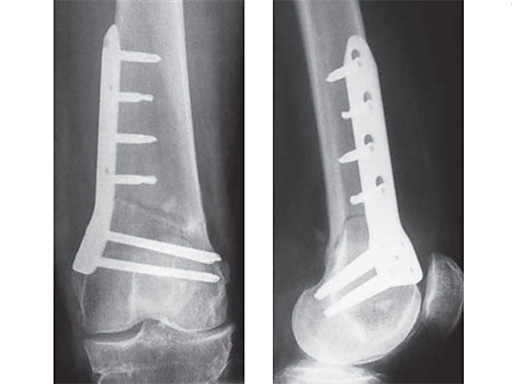

27-year-old male developed severe lateral joint line pain after lateral menicectomy.

Case provided by Philipp Lobenhoffer, Hannover, DE